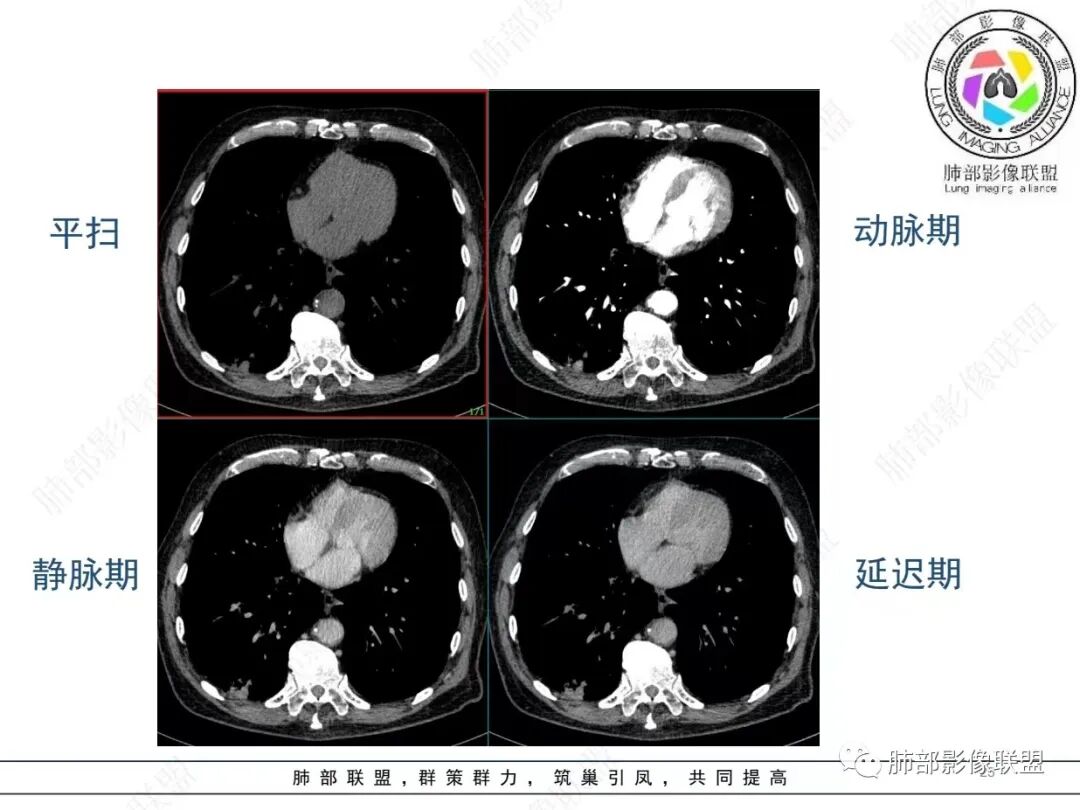

老年男性,发作性气喘,实验室检查白细胞增高。肺部影像表现:右肺胸膜下占位性病变,肺气肿背景,内部可见空腔/空泡影,周围可见小结节,增强动脉期明显强化,静脉期及延迟期强化减低,右侧肺门可见肿大淋巴结,有吸烟史,近年减少,首先考虑恶性肿瘤,肺小细胞癌/鳞癌,隐球菌作为鉴别诊断,病例穿刺活检。

老年男性,肺气肿病史,支气管束增粗,管壁增厚,右肺下叶后基底段胸膜下肿块,土豆征,边界清,有膨隆,小支气管边缘阻断,见集血管束征,肿块强化明显(快进快出特点),并偏心空洞,胸膜下栽赃,周围肺结构破坏(蜂窝状影表现),右肺门淋巴结转移肿大,血管内皮生长因子偏高,肿块与小支气管,血管束关系密切,强化特点,定恶性肺肿瘤,小细胞Ca。

老年男性,肺气肿,右肺下叶胸膜下结节,边缘毛躁,周围多发间质增厚,临近胸膜下脂肪间隙模糊,增强后动脉期不均匀强化,延迟期强化较低,右肺门肿大淋巴结,考虑恶性,鳞癌,小细胞肺癌,鉴别炎性肉芽肿性结节

右肺下叶胸膜下结节,呈山丘状,生长在慢支肺气肿间质纤维化的基础上,边缘相对光滑清晰,右肺门淋巴结肿大,强化呈速升速降,老年男性,吸烟史,考虑小细胞肺癌,鉴别隐球

老年男性,吸烟史40年,肺气肿背景,胸膜下结节,边缘膨隆,增强后结节内有片状坏死区,右肺门及纵隔肿大淋巴结,考虑恶性,鳞癌?小细胞代排

恶性明确(右肺门淋巴结明显肿大,中心坏死,坏死边界不清楚,胸膜下馒头样肿块,血管集束,支气管阻塞,动脉期明显强化,内部明确的供血血管提示肿瘤细胞密集,局部坏死边界不清,强化快进快出,邻近胸膜强化呈胸膜尾征,提示胸膜受侵),病理符合周围性低分化鳞癌(老年男性,长期吸烟史,肿块强化明显,快进快出,坏死边界不清楚,阻塞性炎症及阻塞性肺气肿,肺门淋巴结肿大,坏死,邻近支气管壁增厚支持粘膜下侵润生长),白细胞总数高,动脉期强化那么明显,腺癌合并感染倒是要高度警惕。

老年男性,吸烟史+肺气肿背景,右下肺胸膜下肿块(坏死+内部血管影+快进快出),右侧肺门淋巴结肿大,考虑:恶性、鳞?高级别腺待排(总体感觉偏软)。

男,80,发作性气喘半年,加重1天。长年大量吸烟史。肺部CT:肺气肿背景,右肺胸膜下实性占位,处于外周大疱带与气肿带交界,山丘征,边缘膨隆,边界较清,血管集束,周围可见小结节。增强不均匀强化,内可见迂曲模糊血管影,右肺门、隆突下可见肿大淋巴结。首先考虑恶性肿瘤,小?鳞?鉴别PC、TB等。